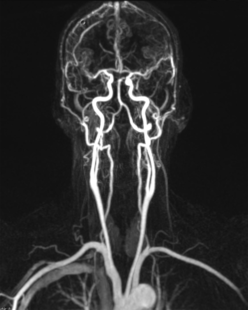

Magnetresonanztomografie:

Die Gefäßdarstellung erfolgt in einem modernen 48-Kanal-Magnetresonanztomografen (Siemens Area 48) der mit spezieller Hard- und Software für die Darstellung aller Gefäße des Körpers ausgerüstet ist. Dazu wird überwiegend ein gadoliniumhaltiges Kontrastmittel verwendet, welches meist über eine Armvene injiziert wird. Die Untersuchung dauert ca. 10 – 20 Minuten.

Neben der Erfassung von Veränderungen des Gefäßdurchmessers zur Beurteilung der Durchblutungsstörung, liefert uns diese Untersuchungsform auch wichtige Information zum Aufbau der Gefäßwände, zum Beispiel bei entzündlichen Gefäßerkrankungen und zum Nachweis von durchblutungsgestörtem Gewebe.

Für Patienten die aufgrund von Erkrankungen kein Kontrastmittel verabreicht bekommen dürfen, besteht durch eine spezielle softwaregestützte Untersuchungsmethode die Möglichkeit, eine Angiografie der Beine auch ohne Kontrastmittelgabe durchzuführen.